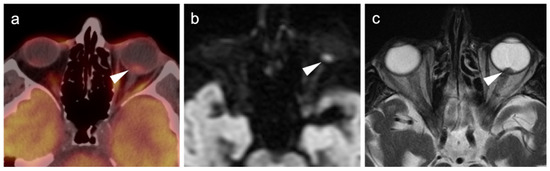

- John, A.R.; Jain, A.; Kishore, B.; Vishnoi, M.; Pandit, A.G.; Sharma, A.; Jaimini, A.; Jain, M.; Singh, A. F-18 fluorodeoxyglucose positron emission tomography/computed tomography in conjunctival melanoma with recurrence. J. Cancer Res. Ther. 2020, 16, 240–242. [Google Scholar] [CrossRef]

- Cassou-Mounat, T.; Luporsi, M.; Huchet, V.; Jehanno, N. Gallbladder Metastasis from Conjunctival Melanoma. Clin. Nucl. Med. 2019, 44, e107–e109. [Google Scholar] [CrossRef]

- Kurli, M.; Chin, K.; Finger, P.T. Whole-body 18 FDG PET/CT imaging for lymph node and metastatic staging of conjunctival melanoma. Br. J. Ophthalmol. 2008, 92, 479–482. [Google Scholar] [CrossRef]

- Keraliya, A.R.; Krajewski, K.M.; Braschi-Amirfarzan, M.; Tirumani, S.H.; Shinagare, A.B.; Jagannathan, J.P.; Ramaiya, N.H. Extracutaneous melanomas: A primer for the radiologist. Insights Imaging 2015, 6, 707–717. [Google Scholar] [CrossRef] [Green Version]

- Wong, V.K.; Lubner, M.G.; Menias, C.O.; Mellnick, V.M.; Kennedy, T.A.; Bhalla, S.; Pickhardt, P.J. Clinical and Imaging Features of Noncutaneous Melanoma. Am. J. Roentgenol. 2017, 208, 942–959. [Google Scholar] [CrossRef]